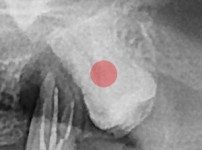

完全埋伏智齿